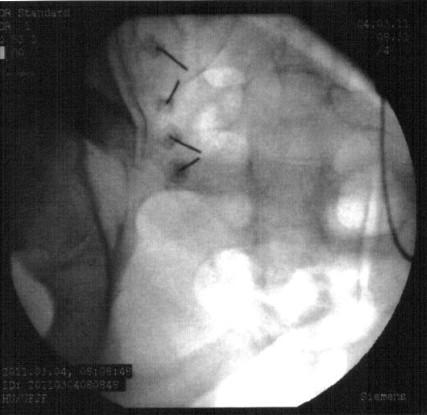

Ao lado, imagem radioscópica exemplificando os forames de S1 e S2 com as cânulas de radiofrequência já posicionadas na emergência dos nervos sacrais de S1 e S2 para procedimento de rizotomia por radiofrequência.

Exemplo dos pontos a serem denervados e anatomia da emergência dos nervos sacrais posteriores de S1 a S3.

Ao lado, modelo anatômico exemplificando os forames de S1 a S3, onde emergem os nervos responsáveis pela sensibilidade dolorosa da articulação sacro-ilíaca.